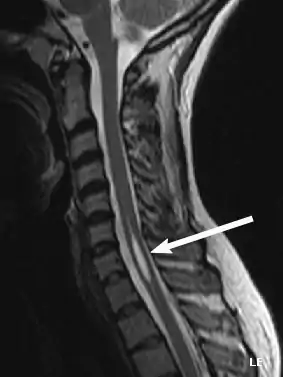

| An idiopathic syrinx | |

Physicians now use magnetic resonance imaging (MRI) to diagnose syringomyelia. The MRI radiographer takes images of body anatomy, such as the brain and spinal cord, in vivid detail. This test will show the syrinx in the spine or any other conditions, such as the presence of a tumor. MRI is safe, painless, and informative and has greatly improved the diagnosis of syringomyelia.[14][15][16][17][18][19][20][21][22][23][24][25]